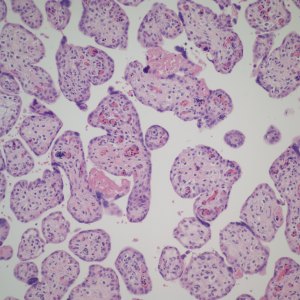

The placental examination demonstrated a marked erythroblastosis (Fig 1). There was mild hydrops. There were no intranuclear inclusions typical of Parvo virus in the nucleated red blood cells, and an immunostain for Parvo virus was negative.